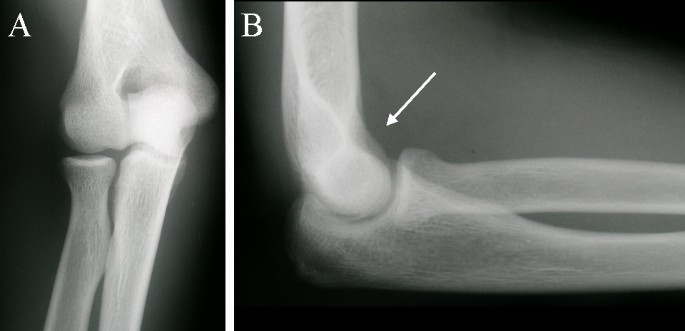

Медицинские аспекты заболеваний: рентгенологическая картина туберкулеза костей

Раздел: Снимки-откровения